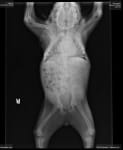

Соцмережами розлетілися фото собаки на прізвисько "Хрюша", що народилася без шиї.

Як повідомляє портал Dogpage, тваринці дуже пощастило в житті. Вона народилася від дикої собаки в лісі. Однак, мати недовго дбала про щеня. Крім того, у малечі виявилося кілька вроджених дефектів: деформація кісток і відсутність шийних хребців.